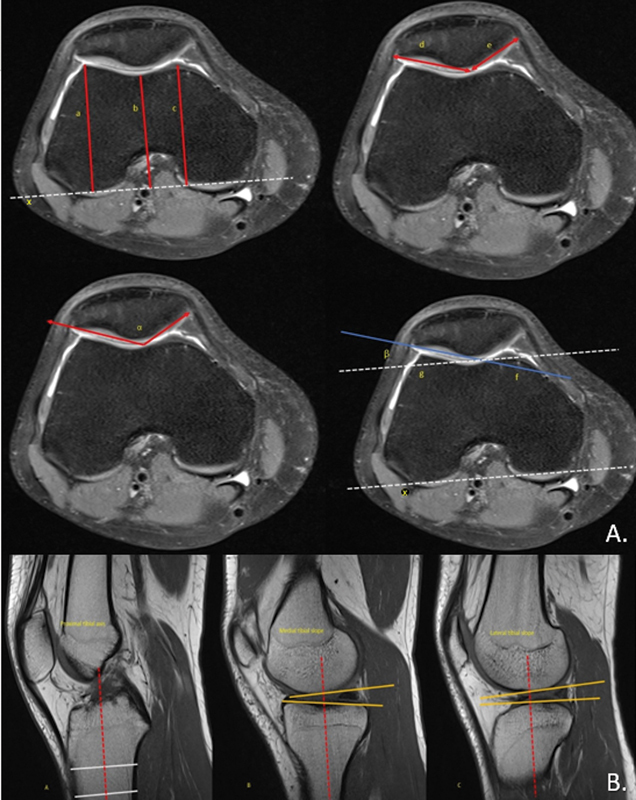

半月板撕裂,尤其是内侧半月板撕裂,在前交叉韧带(ACL)损伤中很常见。修复的前内侧门静脉(RAMP)病变,与前交叉韧带破裂相关的特定半月板损伤,影响内侧半月板后角的外周附着。虽然股骨滑车形态与前交叉韧带撕裂之间的关系已被确立,但其与RAMP病变的关系仍未被探讨。本研究利用磁共振成像(MRI)研究了acl缺失膝的股骨滑车形态与RAMP病变之间的关系,并评估了MRI与关节镜检查的准确性。材料和方法本研究在一家三级医疗中心进行了为期18个月的横断面观察性研究。该研究包括126名接受关节镜下前交叉韧带重建和术前MRI检查的成年患者。变量包括年龄、性别、体重指数、创伤性质和各种MRI参数,包括股骨滑车形态和RAMP病变的存在。将MRI检查结果与关节镜检查结果进行比较以评估诊断的准确性。结果MRI检查21例(16.7%),关节镜检查28例(22.2%)。MRI检测RAMP病变的敏感性为71.4%,特异性为99.0%。股骨滑车形态与RAMP病变无明显关联。然而,胫骨内侧斜坡(TS)和胫骨后内侧骨水肿(PMTBE)与RAMP病变显著相关。MRI与关节镜检查的一致性较高(Cohen’s kappa = 0.773, p)。结论本研究发现,acl缺失膝的股骨滑车形态与RAMP病变无显著相关性。相反,内侧TS和PMTBE是显著的预测因子。与关节镜检查相比,MRI具有高特异性,但敏感性中等。

Introduction  Meniscal tears, especially in the medial meniscus, are common in anterior cruciate ligament (ACL) injuries. Repaired anterior medial portal (RAMP) lesions, specific meniscal injuries associated with ACL ruptures, affect the peripheral attachment of the posterior horn of the medial meniscus. While the relationship between femoral trochlear morphology and ACL tears is established, its association with RAMP lesions remains unexplored. This study investigates the association between femoral trochlear morphology and RAMP lesions in ACL-deficient knees using magnetic resonance imaging (MRI) and evaluates MRI's accuracy against arthroscopy. Materials and Methods  This hospital-based, cross-sectional observational study was conducted in a tertiary care center over 18 months. It included 126 adult patients who underwent arthroscopic ACL reconstruction and had preoperative MRI. Variables included age, gender, body mass index, trauma nature, and various MRI parameters, including femoral trochlear morphology and presence of RAMP lesions. MRI findings were compared to arthroscopic findings to evaluate diagnostic accuracy. Results  RAMP lesions were detected in 21 participants (16.7%) via MRI and 28 participants (22.2%) via arthroscopy. MRI showed 71.4% sensitivity and 99.0% specificity for detecting RAMP lesions. No significant association was found between femoral trochlear morphology and RAMP lesions. However, medial tibial slope (TS) and posterior medial tibial bone edema (PMTBE) were significantly associated with RAMP lesions. The agreement between MRI and arthroscopy was high (Cohen's kappa = 0.773, p  < 0.001). Conclusion  This study found no significant association between femoral trochlear morphology and RAMP lesions in ACL-deficient knees. Instead, medial TS and PMTBE were significant predictors. MRI proved to have high specificity but moderate sensitivity compared to arthroscopy.